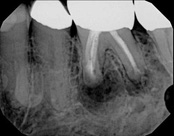

This person presented with one root that had failed from root canal treatment. The arrow in the picture, shows the infection as well as extra filling material that was pushed out of the root. An apical microsurgery was performed using the laser. The infection and excess material was cleaned out. Complete healing is visible 3 months after. The tooth was saved. This is a poor area for an implant.